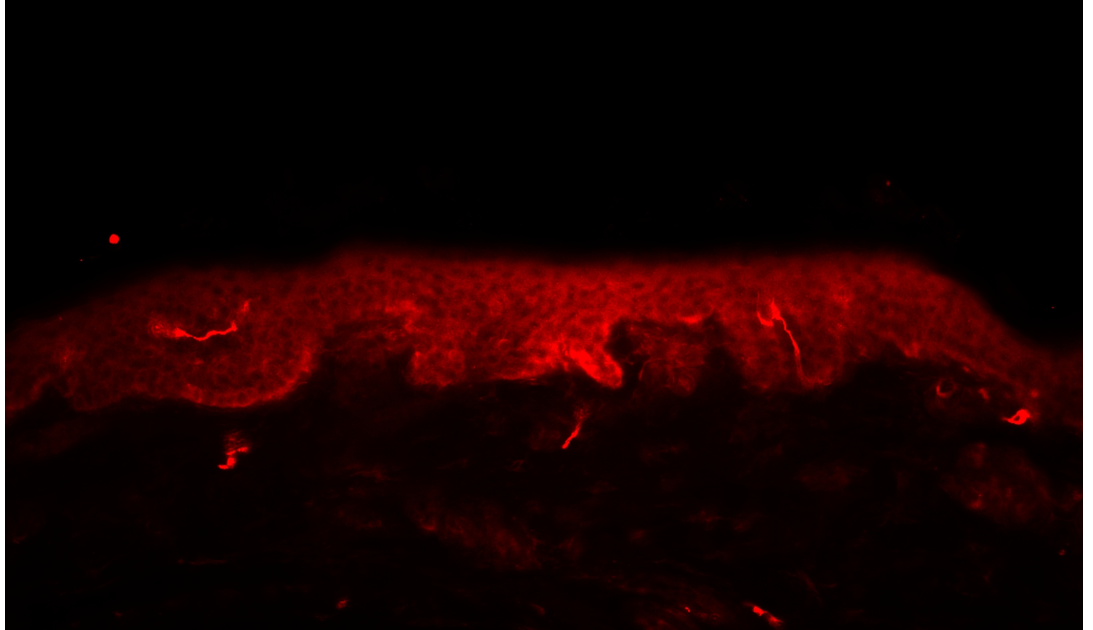

Die Diagnose wird durch eine Biopsie am Unterschenkel aus nicht erkrankter normaler Haut gestellt (3-4 mm Stanzbiopsie nach Lokalanästhesie 10 cm oberhalb des Malleolus lateralis). Das Präparat wird anschließend in spezieller Fixierung an ein Speziallabor versandt.

Ausgezählt werden alle Nervenfasern, welche die epidermale Grenzschicht kreuzen. Bei der SFN ist die Dichte der intradermale Nervenfasern reduziert (Foto PGP9.5 immunhistochemische Färbung).